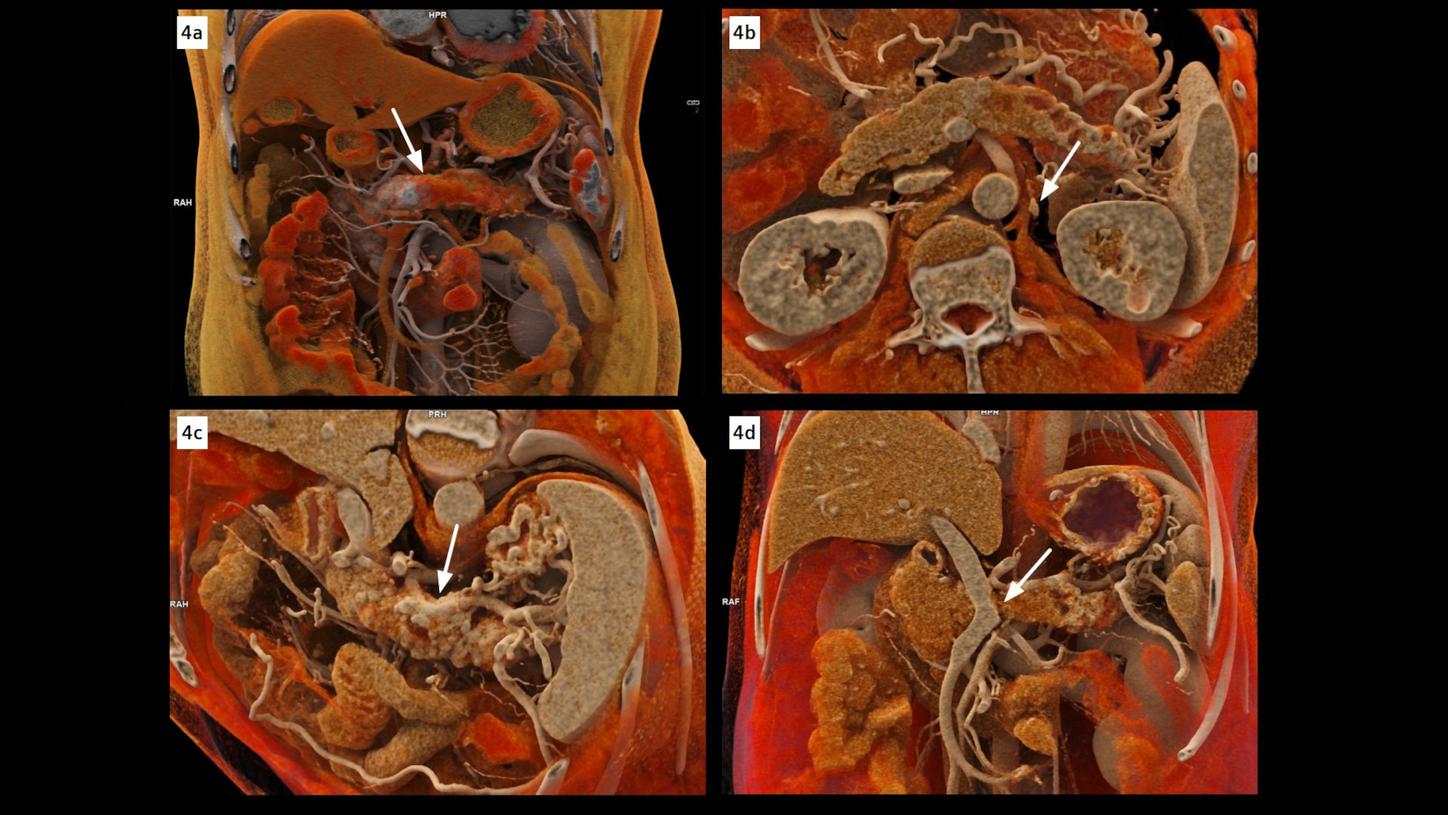

Fig. 4:cVRT images show a distinctly delineated tumor in the pancreatic body (Fig. 4a, arrow), causing notably encasement of the splenic artery (Fig. 4c, arrow), and occlusion of the splenic vein (Fig. 4d, arrow). The left celiac ganglion (Fig. 4b, arrow), thickened and enhanced, is confirmed as a metastasis by pathological analysis after surgery. Images reconstructed at 0.2 mm with a sharp kernel of Bv48 are used to create these cVRT images.